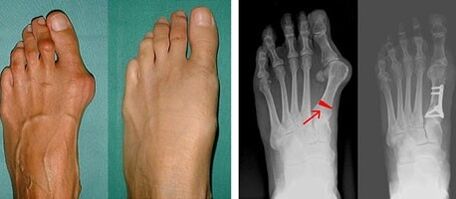

Valgus deformity of the big toe most frequently affects women of mature age, but it also affects men.A deformed base of the thumb does not look aesthetically pleasing.In this case, the person feels physical discomfort and, in the advanced phase, pain.Deviation of the big toe is the result of uneven body loading on the foot.These changes have a detrimental effect on the feet and other toes.

If visual examination and x-rays do not yield any results, the patient is referred for plantography to determine possible flat feet.This method consists of taking footprints, from which shoes or insoles with orthopedic properties are made for the patient.The patient is then prescribed pedometry.This method uses computer analysis to determine the pressure of a person's weight on their feet.The results of advanced diagnostics are the basis for choosing a treatment method for curvature of the first and second fingers.

In the first stage to identify the valgus of the big toe and little finger, the doctor performs a visual examination.In this way, it determines the stage of development of the pathology.To identify detailed changes in the joints, x-rays and plantography are prescribed.